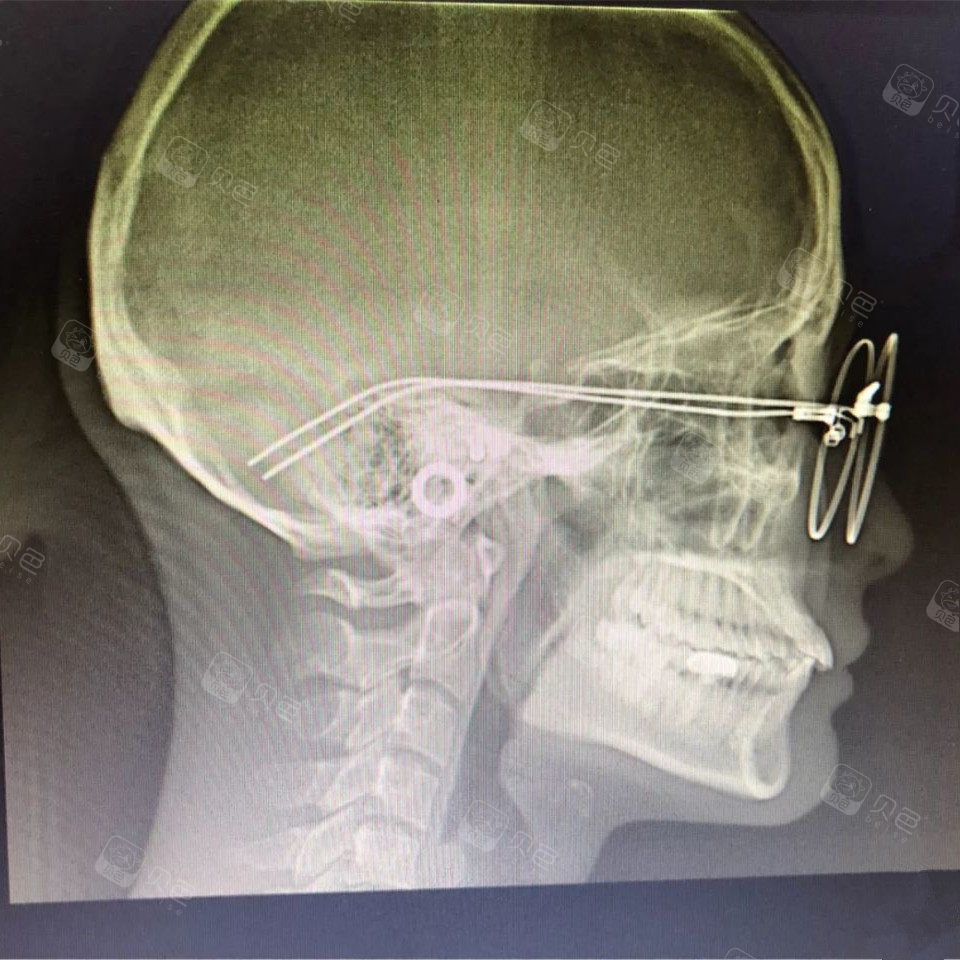

正常牙的牙片图片

正常牙的牙片图片,正常健康的牙片图片

正常健康的牙片图片

正常牙片图

正常牙片